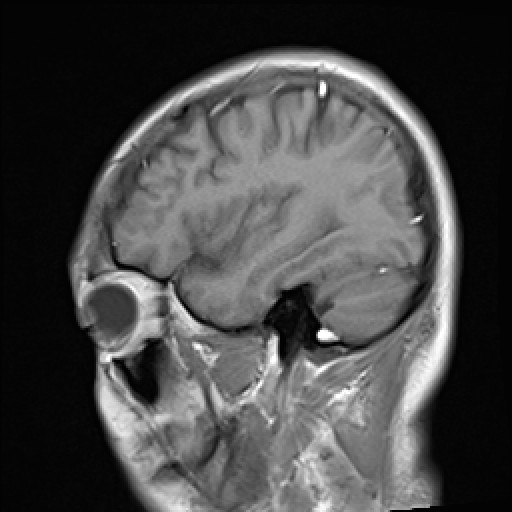

- VILLANUEVA, WILLIAM A. MR HEAD

- VILLANUEVA, WILLIAM A. MR HEAD

- VILLANUEVA, WILLIAM A. MR HEAD

- VILLANUEVA, WILLIAM A. MR HEAD

- VILLANUEVA, WILLIAM A. MR HEAD

- VILLANUEVA, WILLIAM A. MR HEAD

- VILLANUEVA, WILLIAM A. MR HEAD

- VILLANUEVA, WILLIAM A. MR HEAD

- VILLANUEVA, WILLIAM A. MR HEAD

- VILLANUEVA, WILLIAM A. MR HEAD

- VILLANUEVA, WILLIAM A. MR HEAD

- VILLANUEVA, WILLIAM A. MR HEAD

- VILLANUEVA, WILLIAM A. MR HEAD

VILLANUEVA, WILLIAM A. |

239716 |

24/05/1967 |

M |

211062 |

MRI/MRA - HEAD |